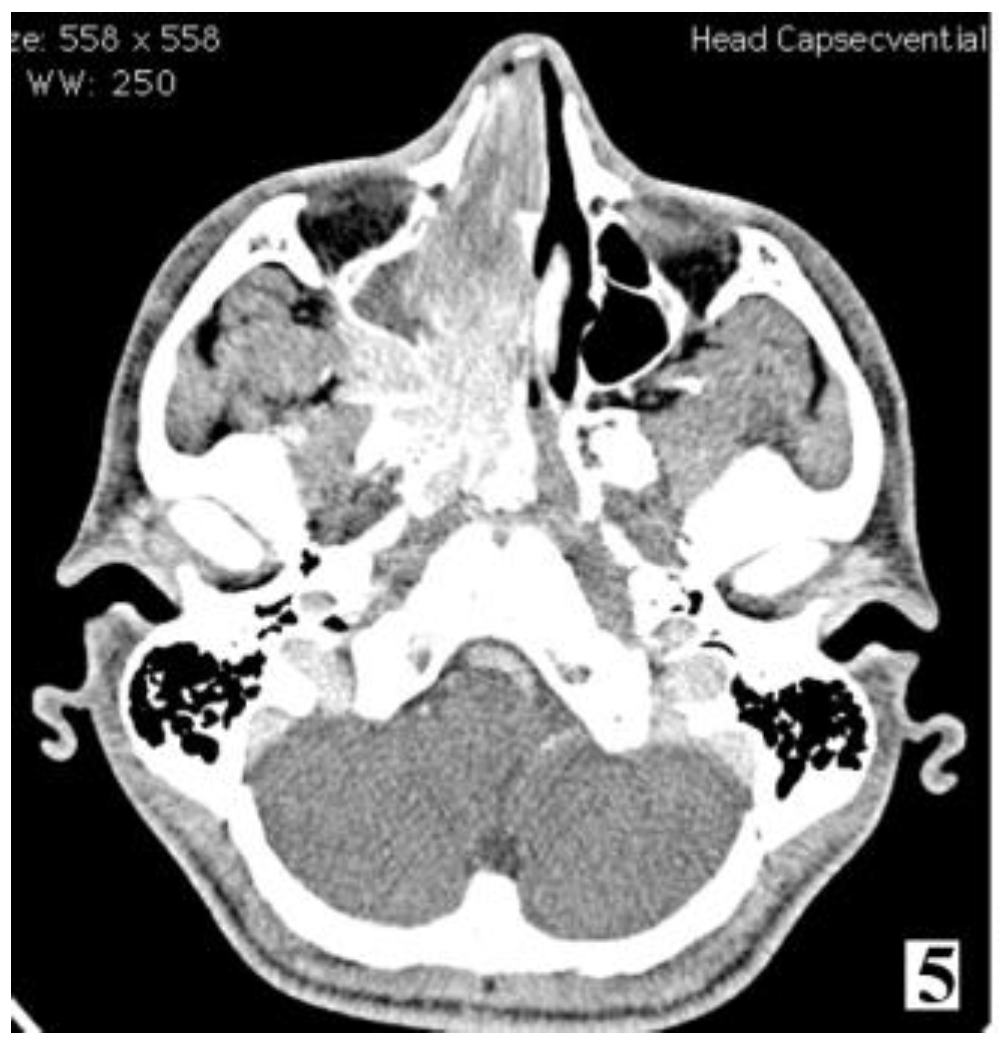

Figure 5. IIA—Minimal lateral extension into the pterygopalatine fossa; IIBFull occupation of pterygopalatine fossa with or without superior erosion orbital bones (part 1).

Figure 6. IIA—Minimal lateral extension into the pterygopalatine fossa; IIB—Full occupation of pterygopalatine fossa with or without superior erosion orbital bones (part 2).

Management of stage IIC cases, with extension into the infratemporal fossa or extension posteriorly to the pterygoid plates, can be done by transnasal approach alone or by a combined approach. Preoperative embolization is mandatory for identifying the vascular feeding source and reducing intraoperative bleeding.

Figure 7. Preoperative MRI of a stage IIC juvenile angiofibroma. The Holman-Miller sign (the anterior bowing of the posterior maxillary wall) on the CT scan (part 1).